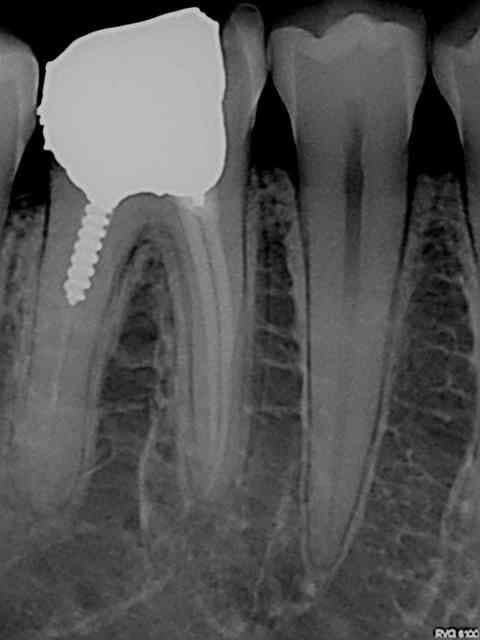

Exemples routiniers d'une banalité affligeante......

R24 kuiaas - Eugenol

R26 urwzsa - Eugenol

R8 q2dwjf - Eugenol

R14 d5xuv9 - Eugenol

Pepsi tmi4vp - Eugenol